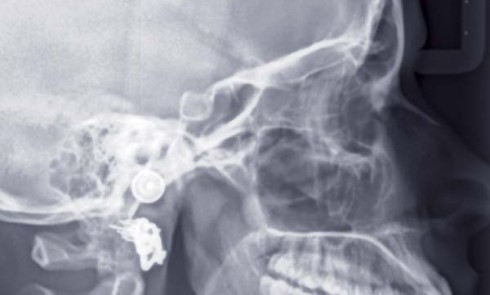

Article réservé à nos abonnés Traitement ortho-chirurgical accéléré par Piezocision™ d’une classe II chez l’adulte

PrésentationLa patiente âgée de 40 ans présente une classe II bilatérale associée à une dysharmonie dento-maxillaire modérée et à une...